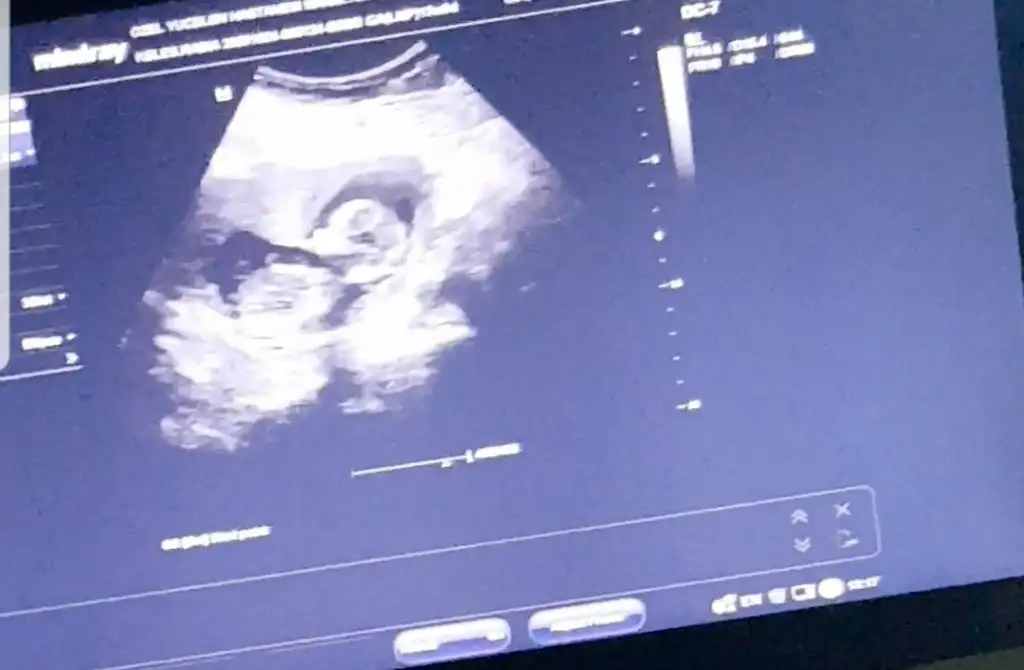

Ya benim içime nedense erkek doğdu kemik yapısını oğlumun usg sine benzettim:)))Bebeğin düz durduğu videodan ben çektim umarım doğru pozisyonu yakalamışımdır. Doktor bir tahminde bulunmadı 13+0 merak ediyorum artık

Artık kız erkek öğrenmek istiyorum ya doktor bir tahminde bile bulunmadı. Artık 28 Aralığa kaldı öğrenmem. Yazarım cnm burayaYa benim içime nedense erkek doğdu kemik yapısını oğlumun usg sine benzettim:)))

Keseye göre Karındansa erkek vajinalse kızTahmini olan var mı insan ikinci çocuk bile olsa merak ediyor